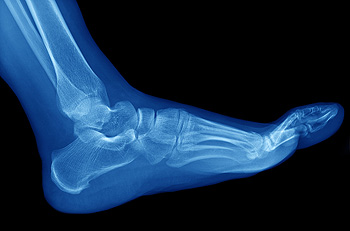

How the Foot is Structured

The relationship between the foot and the lower leg in motion is called foot biomechanics. When the foot is structured correctly, routine activities such as walking and running should typically occur without pain. The foot and ankle combine flexibility with support, providing functions that include shock absorption of one's body weight. Additionally, this part of the body acts as a lever during the push-off period before taking a step. There are 26 bones located in the foot and ankle; these bones are maintained by ligaments and tendons, helping the arches “give” when weight is placed on the foot. Functions of the arches include supporting the weight of the body while standing. The structure of the foot is anatomically linked, resulting in even distribution throughout the foot during weight-bearing activities.